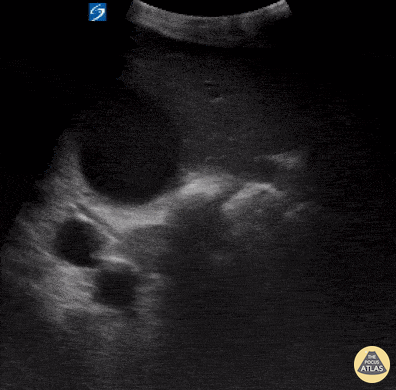

Biliary - Distended Gallbladder

Elderly male with history HTN, DM presented with jaundice and elevated LFTs, bilirubin, and alkaline phosphatase. POCUS showed distended gallbladder with normal wall thickness, and some areas of increased echogenicity in the gallbladder which may represent debris. Patient was later found to have a proximal pancreatic mass likely compressing bile ducts and causing distention of gallbladder and elevated lab findings. Hannah Gadway MS4 Therese Mead, DO, RDMS, FACEP  Central Michigan University College of Medicine